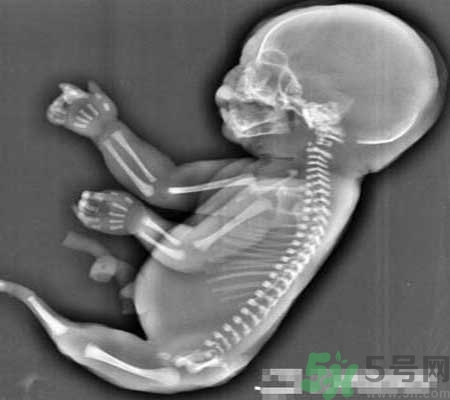

當(dāng)時(shí)經(jīng)超聲檢查發(fā)現(xiàn),孕婦宮腔內(nèi)未見羊水暗區(qū),借助胎兒骨骼影像順序連續(xù)掃查,發(fā)現(xiàn)胎兒頭顱、胸腔、雙上肢,也可以看到一個(gè)跳動(dòng)的心臟。但下肢只找到一條股骨,未見雙腿、膀胱,只有一側(cè)發(fā)育不良的腎臟。

美人魚綜合癥是一種極其罕見的先天性下肢畸形疾病,6萬~10萬人中才有1例,患病的新生兒出生后只能夠存活幾個(gè)小時(shí)。關(guān)于其病因至今仍是個(gè)謎,但醫(yī)學(xué)專家認(rèn)為可能和遺傳基因有關(guān)?;颊哂捎谘貉h(huán)系統(tǒng)在子宮中沒有正常發(fā)育,從而導(dǎo)致她們的腎臟和其他器官也沒有發(fā)育完整。